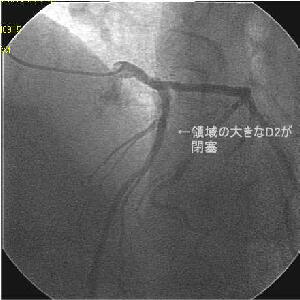

Crush�̎�Z�B

|

|

|

|